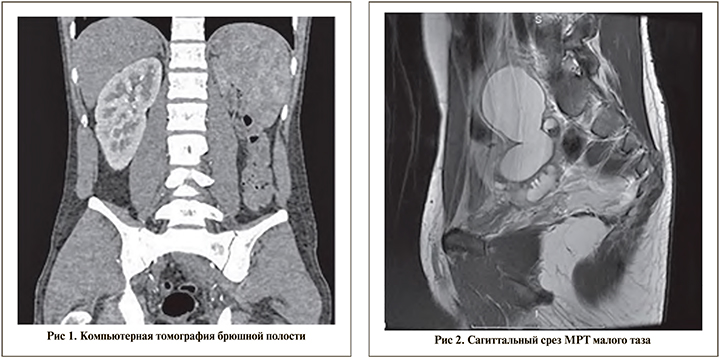

Описание клинического наблюдения. Пациент 19 лет поступил в ГБОУ ГКБ № 31 Департамента здравоохранения города Москвы в экстренном порядке с жалобами на боль в левой половине живота, эпизоды гипертермии до 38С. Из анамнеза известно, что в детском возрасте выявлена агенезия левой почки. При УЗИ обнаружено кистозное образование области малого таза размером 50х38 мм с неровными четкими контурами и слабовыраженной капсулой. При компьютерной томографии обнаружены многокамерное жидкостное образование в малом тазу размером 53х38х103 мм, отсутствие левой почки, гипертрофия единственной правой почки (рис. 1).

С целью дообследования пациенту выполнена МРТ органов малого таза, по данным которой обнаружены киста проксимальных отделов левого семявыносящего протока, расширение проксимальных отделов правого семявыносящего протока, увеличение в размерах и дилатация левого семенного пузырька, расширение левого семявыбрасывающего протока (рис. 2, 3).